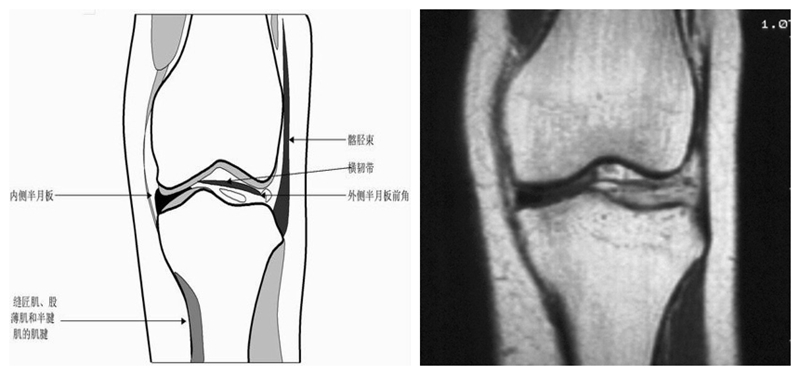

膝关节冠状面MRI解剖

显示内外侧副韧带、腘肌和拱状韧带,有无信号和结构改变,侧重关节胫股软骨的两边和半月板的体部。

冠状位解剖第三层